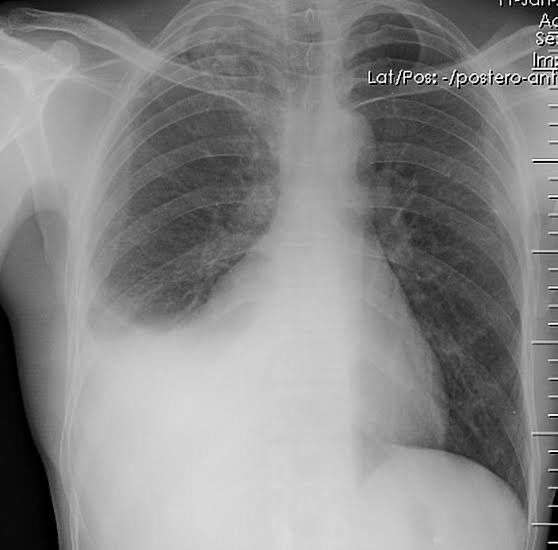

Pleural effusion is defined as the collection of fluid in the pleural space. Fluid can be of two types: TRANSUDATE: Usually clear Protein concentration <30 g/dL Lactate dehydrogenase < 200 U/L LDH fluid : serum ratio < 0.6 Specific gravity < 1.015 It is usually bilateral. Common causes includes: heart failure, hypoproteinemia, constrictive pericarditis, etc. EXUDATE: Usually cloudy or purulent Protein concentration > 30 g/dL Lactate dehydrogenase > 200 U/L LDH fluid : serum ratio > 0.6 Specific gravity > 1.015 It is usually unilateral. Common causes includes: bacterial pneumonia, tuberculosis, connective tissue disorders, etc. Chest X-ray of pleural effusion reveals opacification of the involved area with blunting or obliteration of costophrenic angle on the effected side. In cases of massive effusion, mediastinum is shifted to the contralateral side. Picture credit: https://radiopaedia.org/cases/pleural-effusion-7